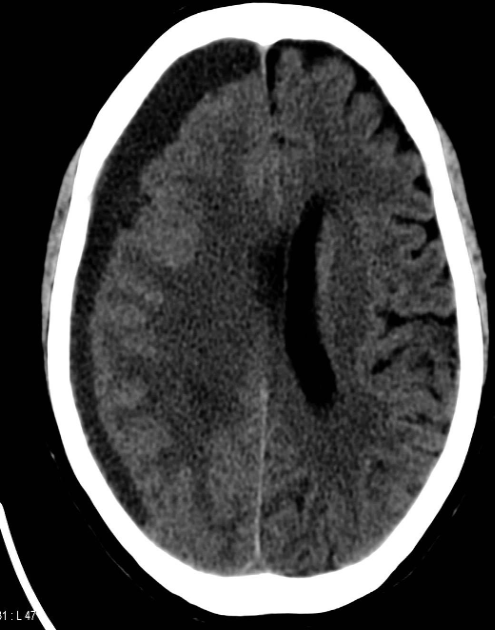

Intracerebral hemorrhage

Infarction appear hypodense on CT without contrast

Sign? Hyperdense sign in stroke; LT Middle cerebral artery hyperintense

Dense basilar artery and middle cerebral arteries on CT

Thrombus in vessel is hyperdense relative to flowing blood